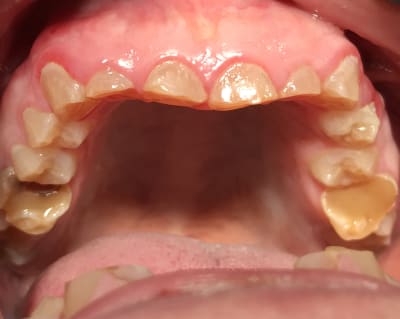

Photos

A82f03fd 2d91 4ef1 97ca f3eb47c7b10d m438gf - Eugenol

780581f7 855e 4bfa 8613 66d779c84307 rrwohx - Eugenol

9db1a8f8 0abe 44f7 87a9 75959bc99136 uojbwk - Eugenol

E2f69a8e 1293 4d24 bc42 b326036451b8 xx21g7 - Eugenol

40edc7b8 ac35 4fb0 a890 d3676a6f086c zc7npz - Eugenol

F210636b b920 48ee 9616 3728267b0311 w3y9lx - Eugenol

poignée de porte a diagnostiqué une maladie genetique, c'est un cas d'amélogenèse imparfaite avec racines courtes, obliteration des chambres pulpaires, émail fin et de mauvaise minéralité pour du collage... necrose en lien avec l'usure (les incisives inf)